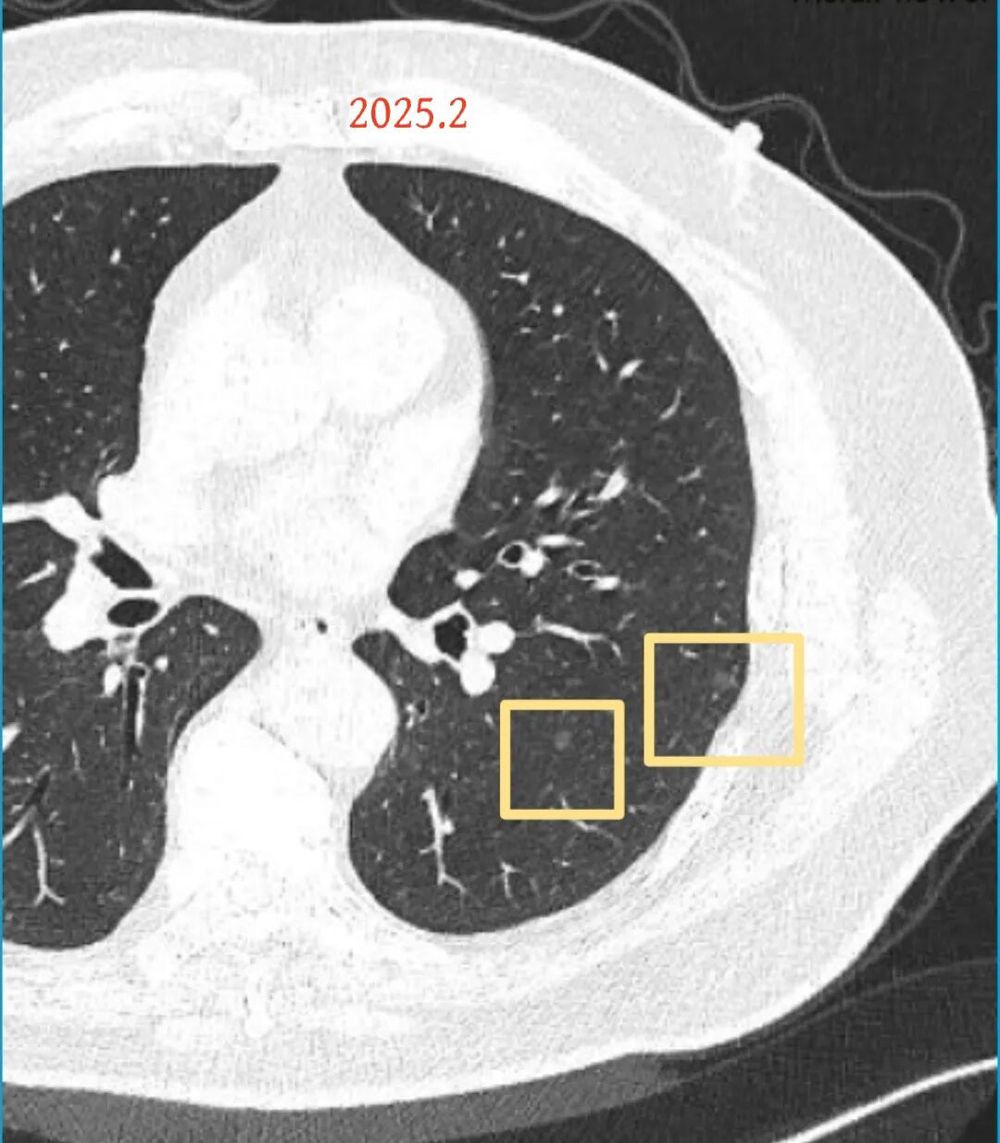

影像展示与分析:

方形的是25年的,红色的主病灶,磨玻璃密度伴少许略偏高点密度,但还说不上典型混合磨玻璃病灶,考虑原位癌或微浸润性腺癌可能性大;蓝色的轮廓与边界欠清,位置靠上叶中央,无法段切或楔切;黄色的多发均淡而纯,分布在两肺。圆形粉色的是主要的两处23年时的样子,对比说不上很明显进展。鉴于若手术得切肺叶,何况两肺他处仍的结节,年纪又74了。我倾向保守点,先6-9个月复查,等进展并风险增加再来考虑怎么办的事。意见供参考!

但病灶B却显然进展!变成以实性成分为主的了!

再看病灶B的2026年3月细节影像特征:

边缘位置也是较淡的磨玻璃成分。

上图是混合密度,轮廓较清,瘤肺边界欠清晰。

病灶A以及他处磨玻璃结节其实进展都是不明显的,略与2022年比,病灶A稍显明显点。病灶B开始时极淡,之前进展虽有但也甚微,直到2025年9月仍是磨玻璃成分为主,只是点状少许密度稍高成分。但在最近半年内却显然进展!若从影像上判断,基本上就得是浸润性腺癌了。那有几点:一是必不能再随访;二是大小来看仍是1A期;三是从快速进展来说,可能含有部分高危亚型,比如微乳头或实体型等;四是他处的磨玻璃结节以及病灶A显然不能用病灶B的转移来解释,仍考虑是多原发早期肺癌。

结友问能否先穿刺?我是这么考虑的:你这个病灶B一是位置深,且靠近附近的血管,不容易穿刺;二是从影像变化来看,基本上肯定是恶性的,不是100%,也是95%以上的概率。刚才我又在重建看冠状位与矢状位以及各次影像,目前混合密度的其实是后来者居上,原来刚开始是它比旁边的病灶密度淡的,但它的密度不是太纯,前次你自己也说似乎有点状偏实性成分。只是最近这半年进展特别快。这说明它的恶性程度较它边上原来就比较明显的那处恶性程度高,亚型中大概率有低分化的成分。所以从目前的影像来看,要尽快手术,而且切肺叶更为稳妥些。